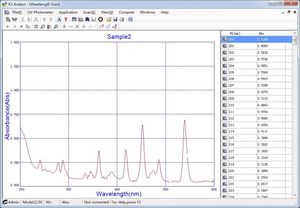

software de análisis de muestrasSamples Inventory Management Software

... El software ayuda en el diagnóstico de condiciones fisiológicas o patológicas mediante la lectura de la intensidad de la tinción de líneas antigénicas en tiras individuales tras la reacción con muestras de suero humano, plasma, líquido ...